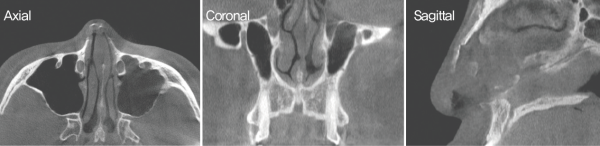

수술 전 CT. 비중격 만곡이 관찰되었다. 또한 비중격 골부에서 좌측으로의 만곡과 비중격 손상으로 인한 안장코 변형이

확인되었다. 측면에서는 이전 수술로 인한 비중격 소실이 관찰되었다.

수술 전 CT. 좌측 미단부에서 심한 만곡으로 인한 비밸브 협착이 관찰되었다.

내원 당시 시행한 CT 상 비중격 미단부와 상단부 연골부의 좌측으로의 만 곡, 비중격 손상에 의한 안장코 변형도 보였다.

비익연 골의 내전과 비중격 좌측 미단부의 변형으로 인해

좌측 비밸브에서의 협착도 관찰되었다.